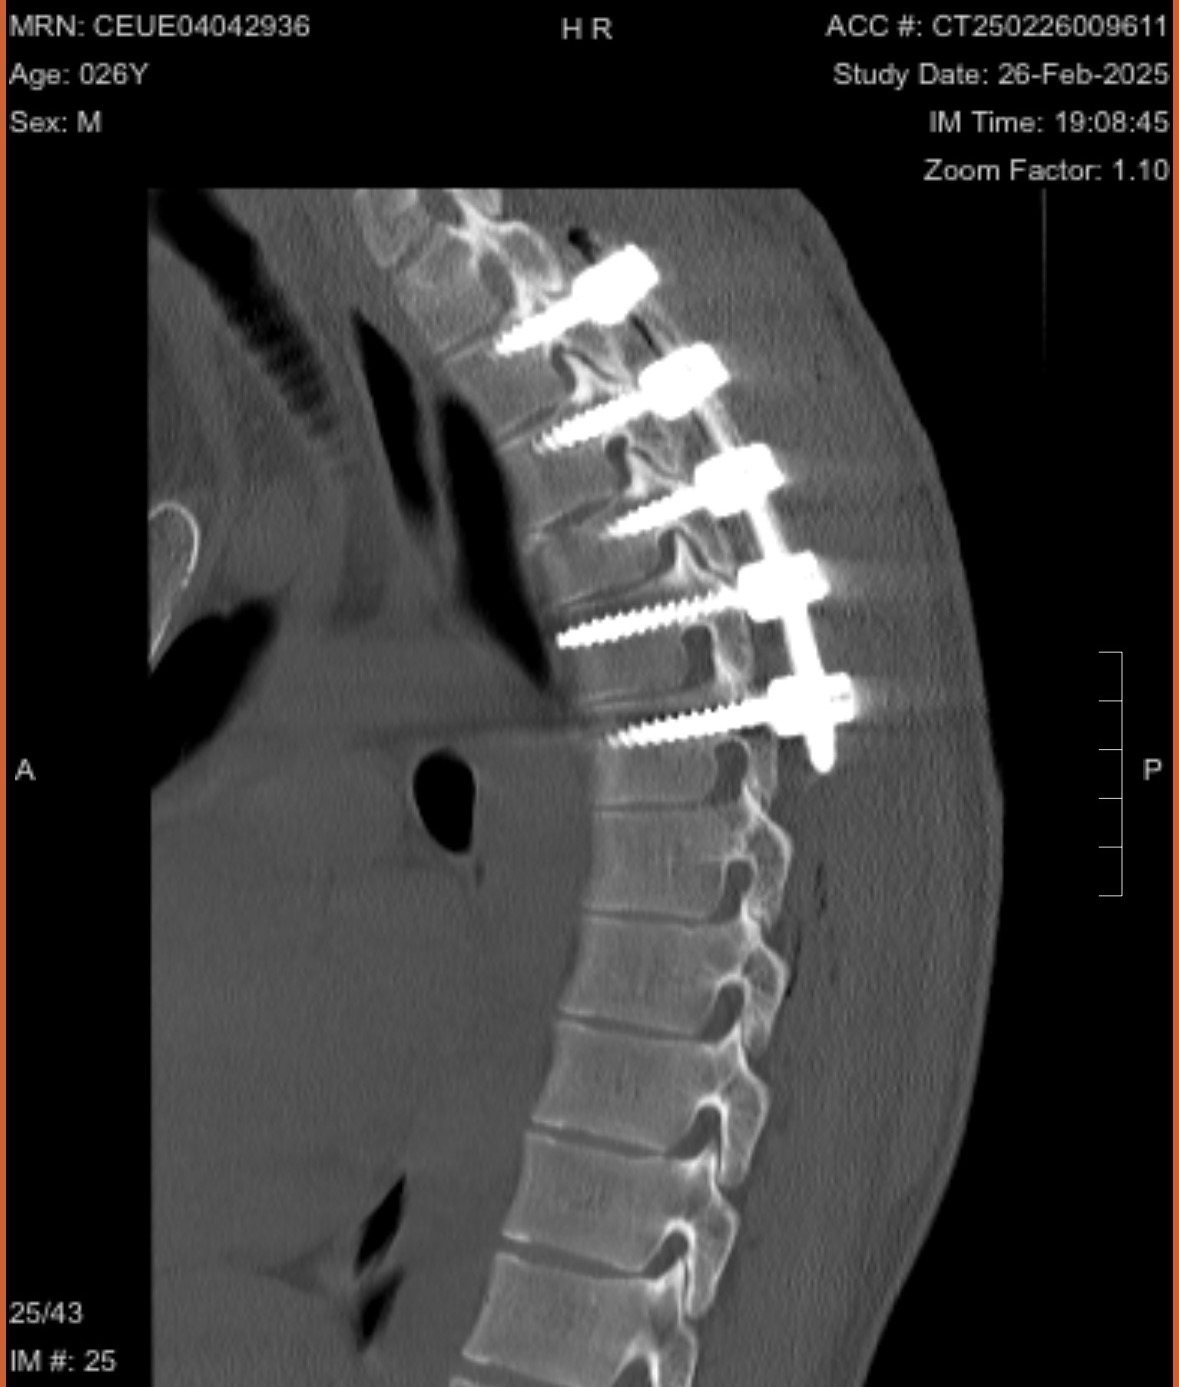

This is my wonderful partner, Danny. Last year while we were on a snowboarding trip in the mountains, he experienced a horrible accident that left him with a broken spine. This was a freak injury, as Danny has been an experienced rider for many years.